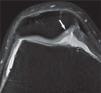

Asimismo, el artefacto por desplazamiento químico se ve reducido mediante el aumento del ancho de banda y mediante la técnica de supresión grasa, quedando bien definida el área de relación entre el cartílago y el hueso subcondral. Con todo ello, encontramos que de manera independiente, tanto el empleo de TR largos, por un lado, como la aplicación de saturación espectral de la grasa, por otro, contribuyen a mejorar el rango dinámico y la RCR. Combinadas ambas técnicas, se consigue en 3.0 T un muy alto contraste fluido-cartílago, de gran importancia para el estudio de posibles lesiones: el efecto artrográfico (figs. 8 y 9).

Imagen coronal en la que se aprecian lesiones profundas en el cartílago articular (flechas grises) y un cuerpo libre (flecha blanca) correspondiente a un fragmento de cartílago desprendido de los espacios señalados con las flechas grises. El alto contraste entre el líquido articular y el cartílago en secuencias ponderadas en densidad protónica con supresión grasa facilita su observación.